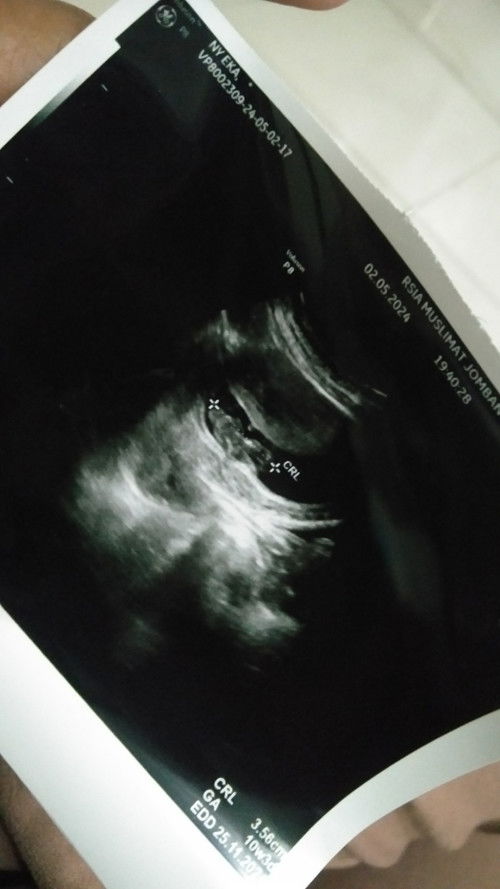

Ada yang sama kah kehamilan 16week jarang terasa pergerakan baby nya??. Soal nya waktu usia kehamilan 6week diUSG hanya ada kantong nya saja. Setelah usia 10week baru muncull janinnya.. Ini USG usia 10week

Hamil 16week jarang kerasa pergerakan baby apakah wajar bun?